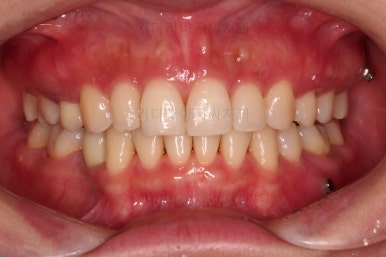

임플란트 보철까지 잘 세팅이 된 후 마무리 하게 되었습니다.

임플란트까지 잘 들어간 후 마무리 했고요.

결손공간 없이 상하좌우 모두 같은 갯수의 치아로 치료가 잘 종료되었습니다.

부산인비절라인 전후 비교해 볼게요.

얼굴에 대한 중앙선도 잘 마무리 되었습니다.

어쨌든 모든 부분에서 인비절라인으로 잘 마무리가 된 환자분이었습니다.

이상 결손치아가 5개 있었고, 비대칭, 유치잔존 환자분을 부산인비절라인으로 교정치료 후 임플란트 2개로 마무리를 한 치료사례였습니다.